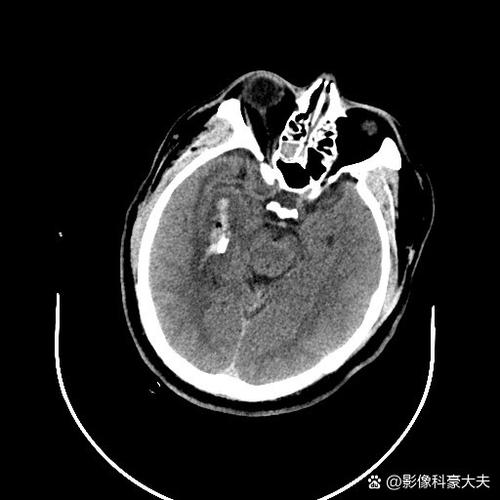

- 梗塞:当某根小动脉完全堵塞后,它所供应的那一小片脑组织就会因为缺血缺氧而坏死,形成一个很小的“病灶”,这个病灶在CT或MRI上就表现为一个“腔隙”,所以称为“腔隙性梗塞”。

- 能发现,但有局限性:新鲜的、稍大的腔梗(通常直径大于5-8毫米)在CT上可能显示为小的低密度灶,很多非常小的、陈旧的腔梗在普通CT上可能看不清楚,或者与正常的脑组织难以区分。

- MRI更敏感:对于诊断腔隙性脑梗塞,磁共振成像(MRI)是金标准,特别是DWI序列,对新鲜的缺血病灶非常敏感,如果CT报告发现了“多发腔梗”,那说明病灶还是比较明确或比较多的,但如果您没有做过MRI,医生可能会建议您做MRI来更准确地评估病灶的数量、位置和新旧程度。